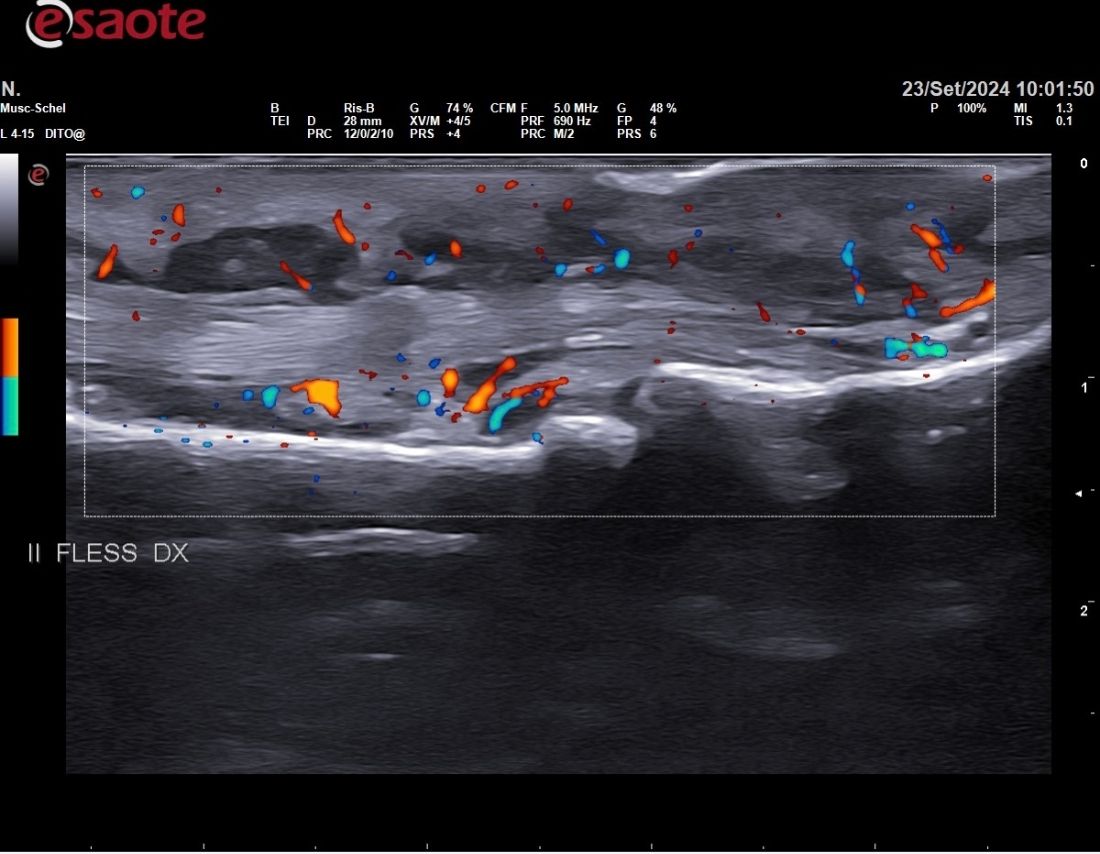

Nel mio percorso formativo ho conseguito esperienza nell'ecograifa articolare, nelle infiltrazioni articolari, nelle biopsie sinoviali e nella gestione delle terapie immunosoppressive con farmaci biotecnologici

• Ecografia osteoarticolare

67 € - 180 €